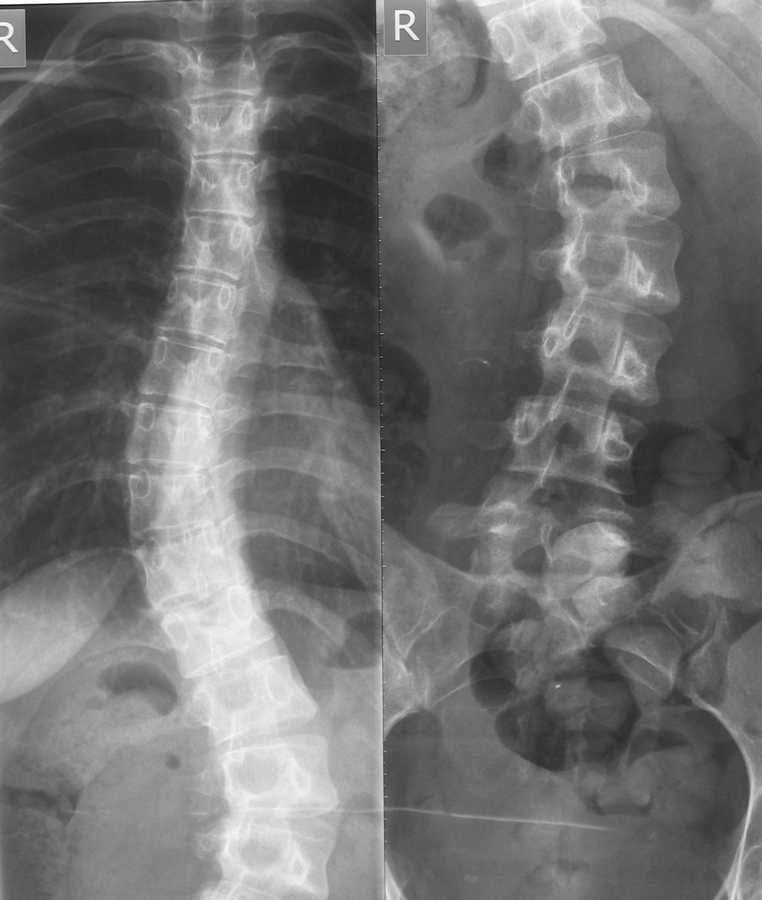

Здравствуйте уважаемые коллеги. Помогите разобраться в ситуации. Девушка 22 года, впервые выявлен сколиоз около 5 лет назад.

Получала несколько раз курс консервативного лечения. На данный момент ситуация видна на представленном снимке. Клинически проявляется только в косметическом дефекте, боли не беспокоят. имеет ли смысл устранять косметический дефект хирургически,если - да, то на какой базе?

С некоторым домысливанием можно сказать, что у пациентки имеется:

1. Компенсированный (сбалансированный) сколиоз

(лордо? кифо?сколиоз – нет боковых снимков)

2. D25°-S29°

3. Кинг-I?(нет функциональных снимков)

4. Риссер-5

5. Таннер Т5-P5

6. Рост пациентки - ?

7. Болевого синдрома, выраженных дегенеративных изменений в позвоночнике нет

Предположим, что пациентка уговорила доктора, а доктор уговорил пациентку на операцию по косметическим показаниям.

Деформация типа кинг I c выраженным искривлением поясничного отдела, ротацией поясничных позвонков, клиновидной деформацией L1,4,5, требует включение в спондилодез как минимум L4 позвонка для сохранения баланса туловища. Верхний уровнень спондилодеза ориетировочно Т5.

Вентральная мобилизация и передний спондилодез в даном случае не показаны.

Добавит ли косметичности разрез по всей спине, можете ли вы прогнозировать отстутствие хронического болевого синдрома и осложненйи. связанных с операцией. Думаю нет, поэтому считаю оперативное лечение не показанным.